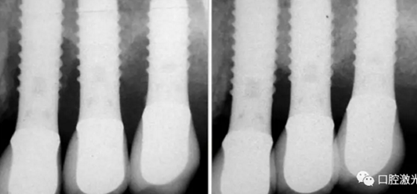

激光非手術(shù)種周炎治療前與治療后2年的對比